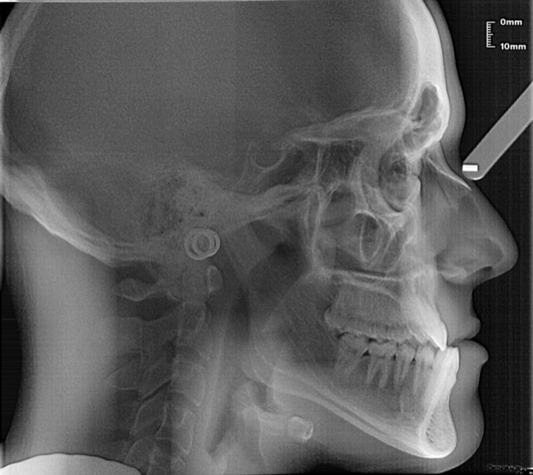

On-Demand CE Guidelines for Orthodontic Evaluation and Preparation for Orthognathic Surgery Patients

Miguel Hirschhaut, DDS; and Carlos Flores-Mir, DDS, DSc Credits: 2 SI Cost: $16 Provider: AEGIS Publications, LLC Dates: Through Feb. 28, 2025 |